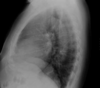

Observa y nombra la silueta de las diferentes estructuras que forman el mediastino en radiografía lateral.

Mediastino en radiografía lateral.

A: Corazón. B: Cayado aórtico. C: Tráquea. D: Hilio. E: Ángulo costofrénico. F: Diafragma izquierdo. G: Diafragma derecho. H: Hígado. I: Burbuja gástrica.